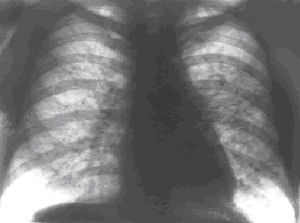

Рис. 3. Рентгенограмма грудной клетки больного саркоидозом легких.